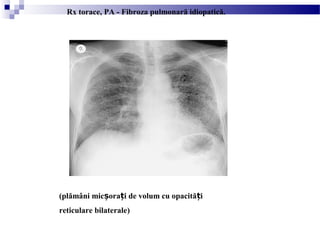

Fibroza pulmonară intersti ialăț

(plămâni mic ora i de volum cu opacită iș ț ț

reticulare bilaterale)

Rx torace, PA - Fibroza pulmonară idiopatică.